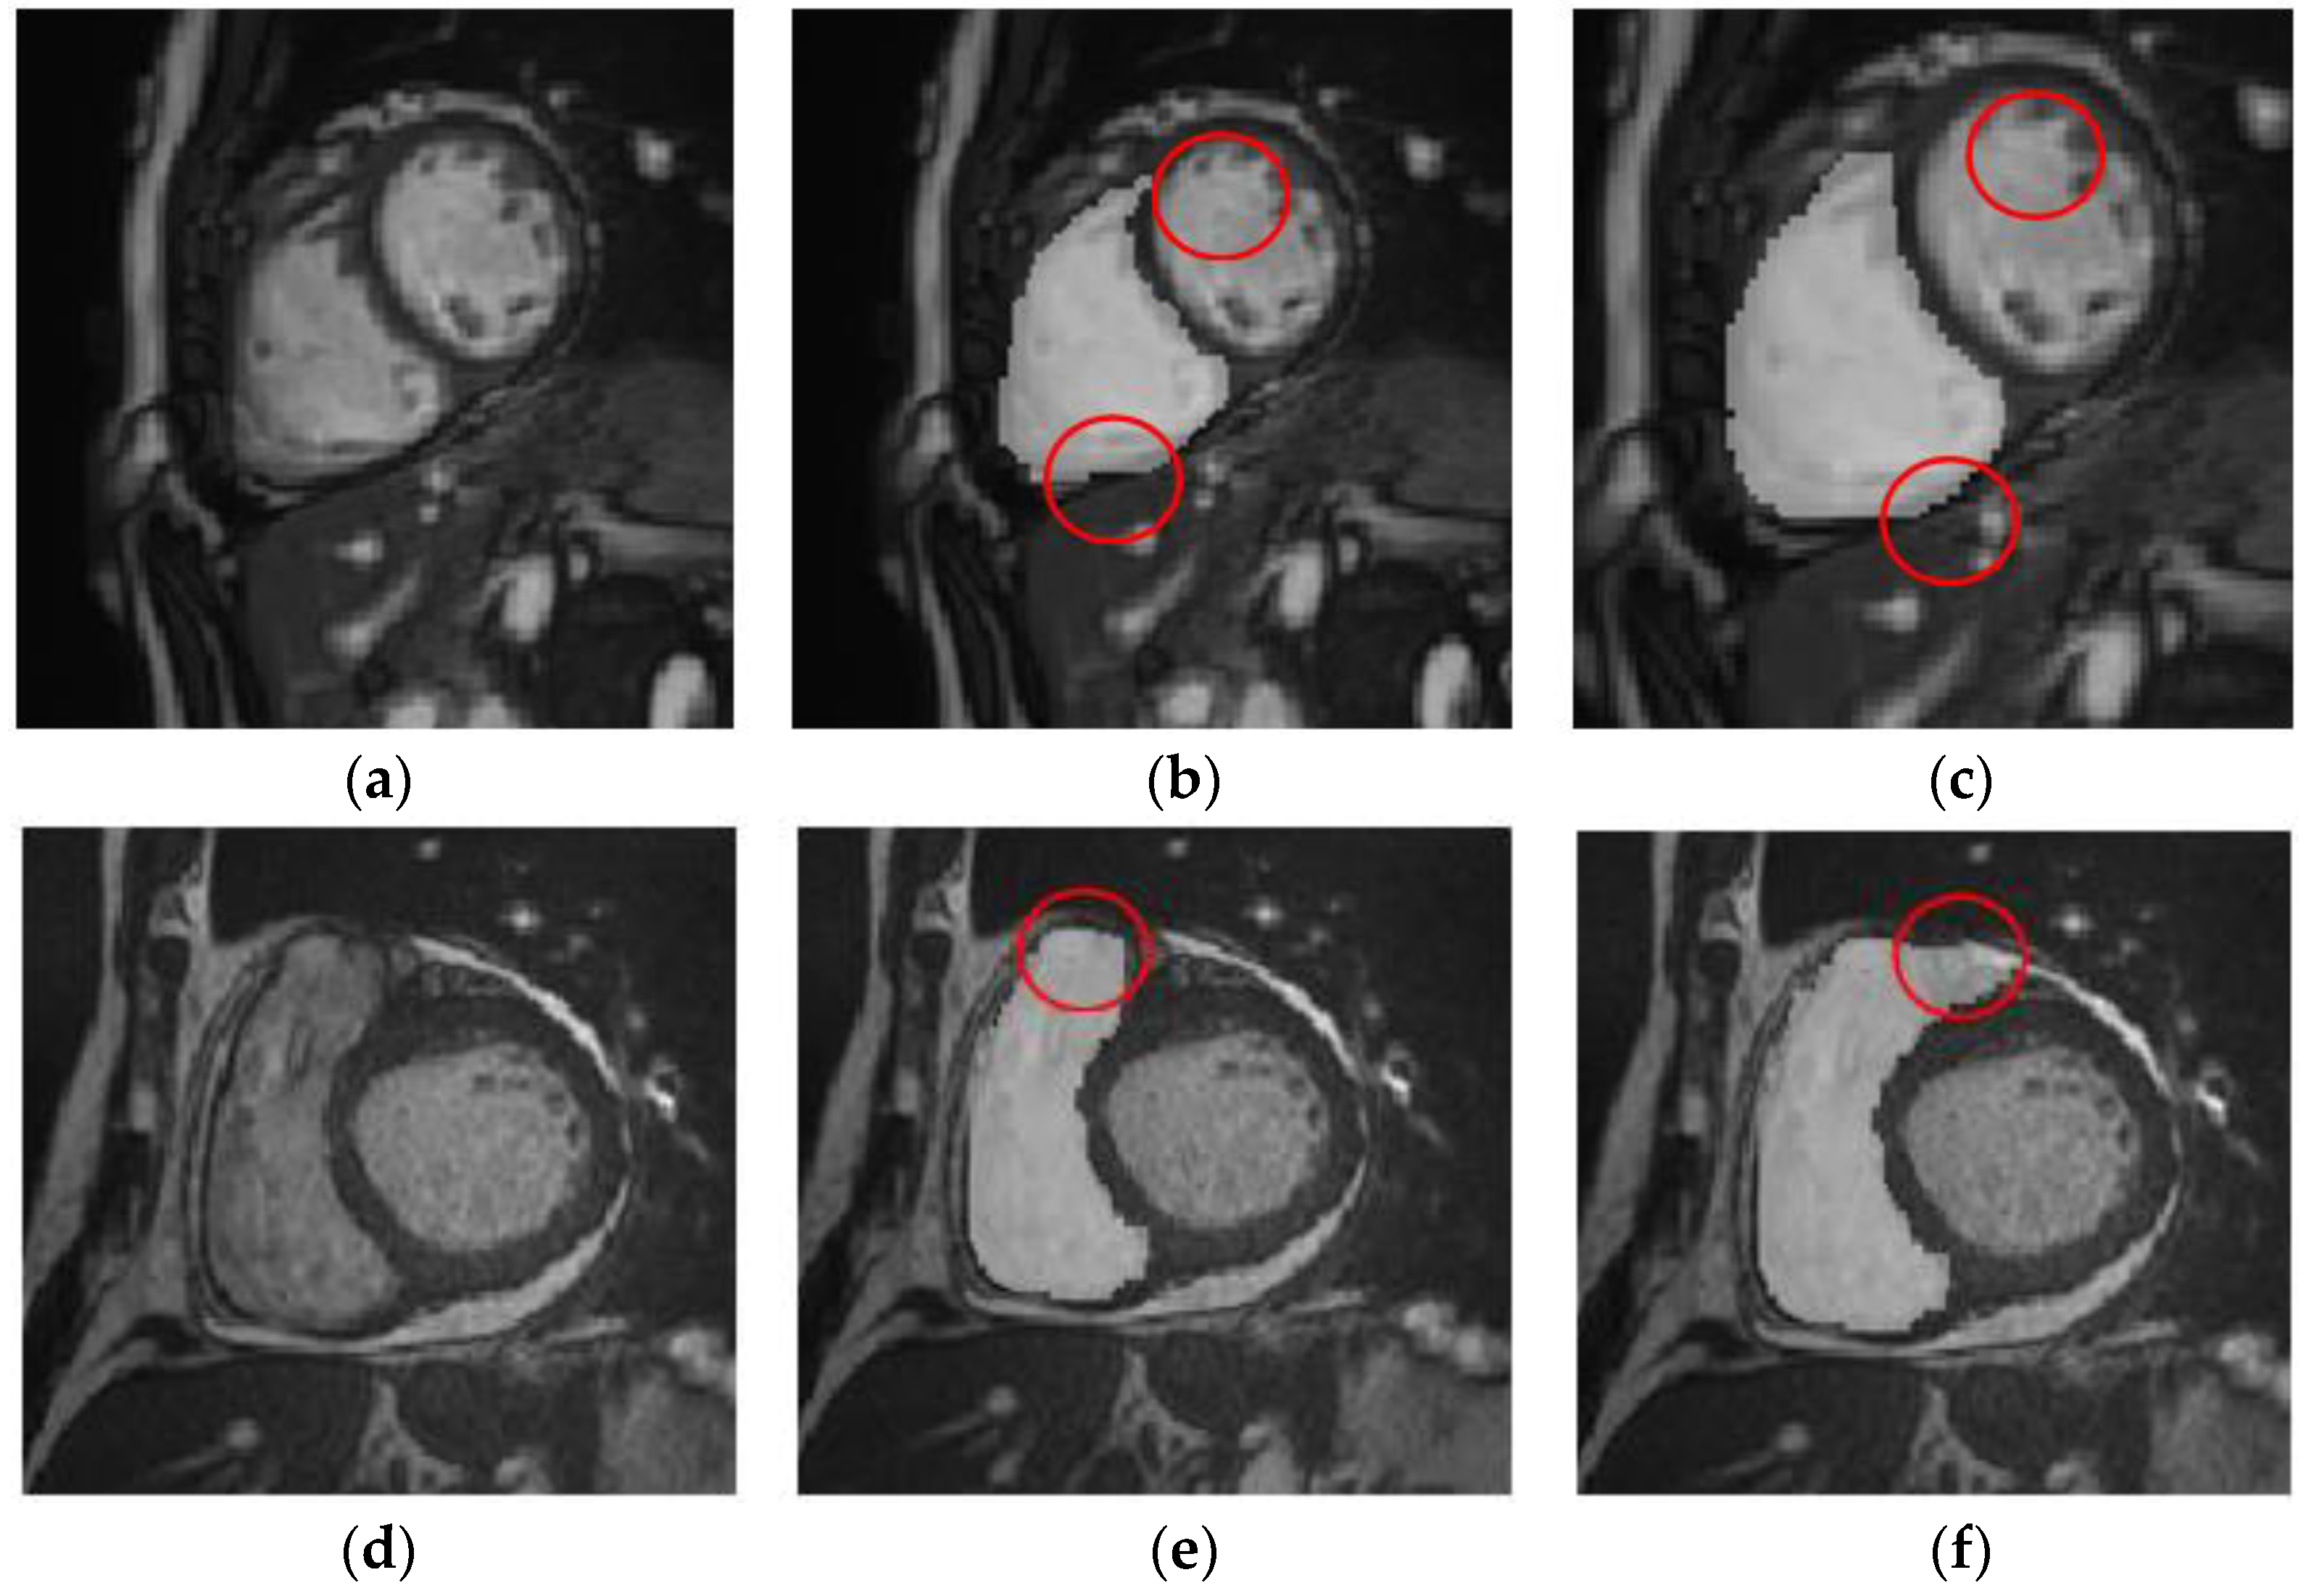

At present, cardiac MR imaging is one of the most important, accurate, and noninvasive diagnostic tools for imaging cardiac structure and function. Doctors usually analyze a patient’s cardiac MR images and calculate the continuous dynamic changes in the left and right ventricular volumes in the process of contraction and relaxation. This approach can be used to determine parameters, such as cardiac end-diastolic and -systolic volume, stroke output, and ejection fraction, to judge an individual’s cardiovascular health status. Therefore, accurate segmentation of ventricles in such imaging is very important. A cardiac MR image is shown in Figure 1.

Figure 1. MR image of the heart.